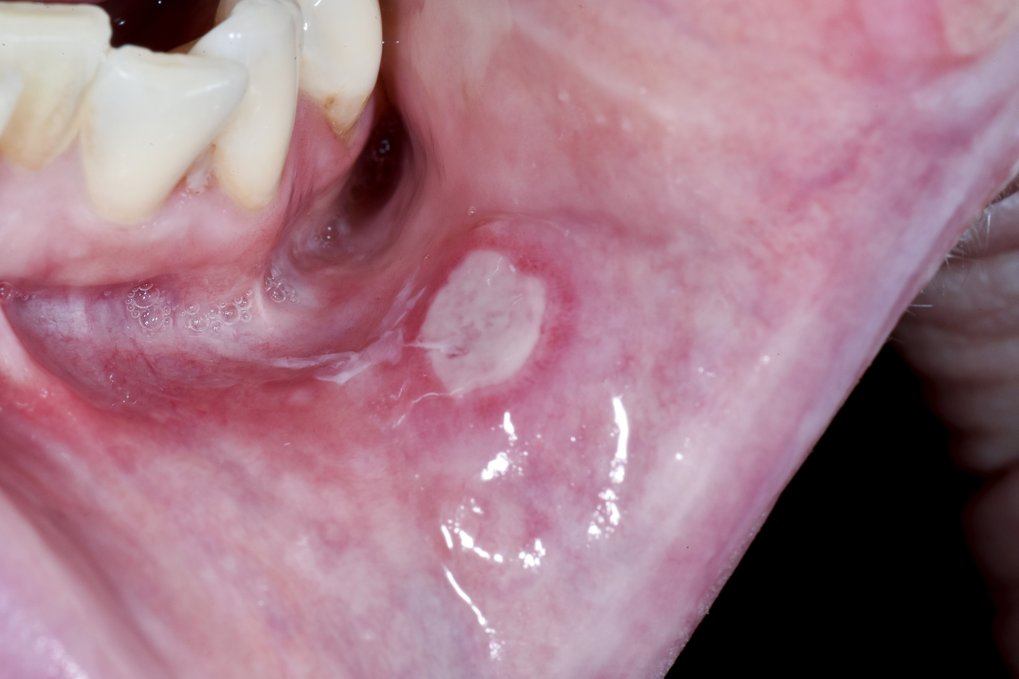

大家有嘴巴破洞的經驗嗎?小編之前嘴巴破掉超痛去看醫生,被叮嚀要早點睡覺,因為當時嘴破是抵抗力不足導致。然而,如果嘴巴有破洞卻感覺不到疼痛,甚至口腔出現不明腫塊,就要非常小心了,這些可能都是口腔癌的病徵。

蔡醫師也提醒口腔癌初期的症狀痛感輕微,較不容易自覺,常見「口部有不明腫塊、嘴破、口臭、無痛潰瘍」等症狀。若是已經出現「口腔不正常出血、吞嚥困難、口腔活動受限、無痛頸部腫塊」等4症狀,恐怕已經進入晚期了。蔡醫師呼籲有抽菸、嚼檳榔的高風險族群定期篩檢。根據國民健康署,30歲以上嚼檳榔 (含已戒檳榔) 或吸菸民眾, (嚼檳榔包含已戒之原住民可提前至18歲起接受檢查) ,每2年可免費1次口腔黏膜檢查。